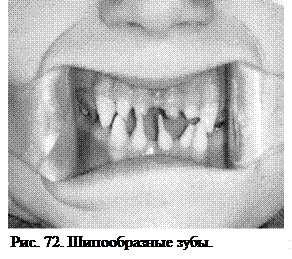

Шипообразные зубы (Рис. 72). Такая аномалия формы зубов встречается в виде рудиментарных верхних боковых резцов, реже центральных резцов. Частичное отсутствие зубов и их зачатков у детей является следствием нарушений развития органов эктодермального генеза (эктодермальная дисплазия). Такая врожденная патология приводит к различным по степени тяжести нарушениям развития и роста зубов, вследствие чего возможны самые разнообразные нарушения их формы. Шипообразные зубы обнаруживаются при расщелине неба, когда боковой резец расщеплен на два шипообразных зуба. Нарушение формирования зубного ряда при этом виде аномалии выражается в наличии промежутков между зубами, так как по своей величине такие зубы меньше нормальных.